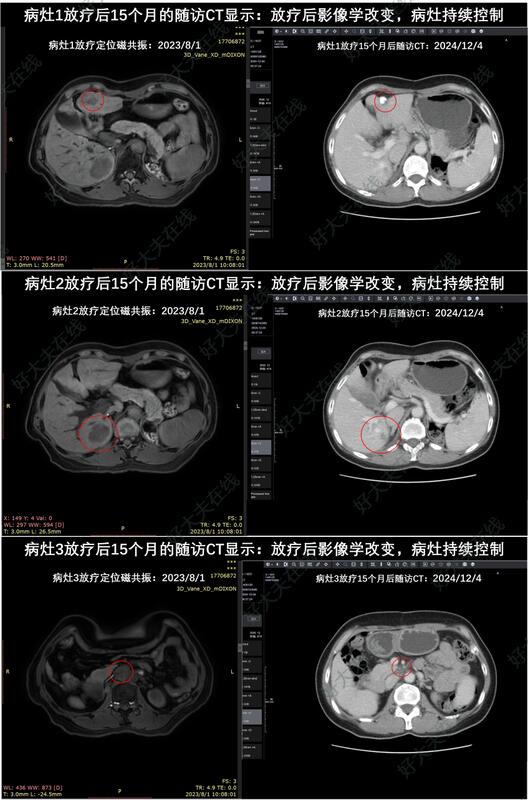

分享一例肝癌寡转移3病灶(肝内2病灶+腹膜后淋巴结)SBRT放疗后长期受控的案例。

2023年7月外院CT示:肝内多发病灶,右肝后叶占位较前增大;腹膜后淋巴结转移。患者赴我院寻求放疗。

患者于2023年8月完成SBRT放疗:50Gy/8Fx(处方BED=81.3Gy,3个PTV内平均BED依次为112.6Gy,107.5Gy,96.4Gy)。

放疗后18个月的随访CT显示:放疗后影像学改变,3个病灶都持续受控。患者肝功能正常,目前生活质量良好。